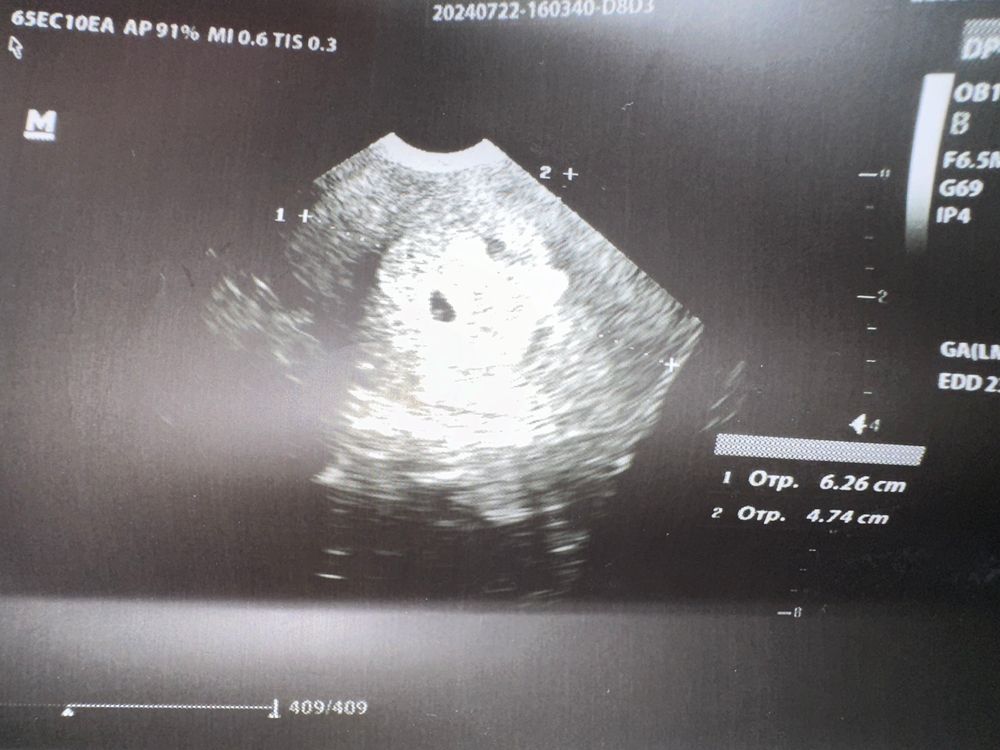

Завтра ровно 6 недель по М. В понедельник была на узи, что бы удостовериться в маточной Б. Все хорошо, СБ конечно еще не было, но все ок. Прописали витамины, отправили домой. Самочувствие хорошее, не работаю. В меру гуляю, ни токсикоза, ни болей. В общем идеальное состояние.

говорю как два? Вот же УЗИ в понедельник делала, смотрите. (См фото ниже). Она - ну вот же и тут видно, что их 2. И правда вижу. Почему мне тогда не сказали? Узи платно делала, видимо такой врач… Если бы сразу пила утражестан, смогла бы двоих сохранить, а так видимо не судьба.